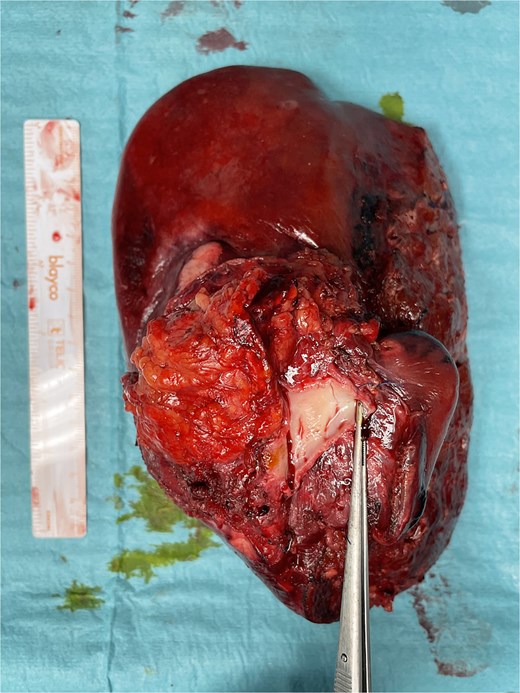

A 42-year-old asymptomatic male patient was referred with a suspicious liver mass detected on abdominal ultrasound (US). The US was made after a blood test revealed an isolated elevation of gamma-glutamyl transferase of 789 IU/l. Past and family history were unremarkable. Computed tomography (CT) scan revealed a large tumour measuring 12.6 cm occupying the right liver (Fig. 1 and Supplementary Video S1). Magnetic resonance confirmed a heterogeneous, ring-enhancing hepatic lesion with obliteration of the right hepatic vein (RHV), and invasion of the middle hepatic vein (MHV), PV, and the retrohepatic portion of the IVC. No metastatic lesions were present. Tumour markers and endoscopic exams revealed no alterations.

CT scan of the intrahepatic cholangiocarcinoma before chemotherapy. (A) Axial CT scan of the intrahepatic cholangiocarcinoma centred in liver segments 5, 7, and 8, with extension to segment 1 and invasion of the PV and IVC; (B) coronal CT scan view of the vascular relation between the cholangiocarcinoma and the IVC; and (C) vascular invasion of the PV.

The patient was discussed at a multidisciplinary meeting for suspected intrahepatic cholangiocarcinoma. Due to the tumour size and macrovascular invasion, the patient was proposed for neoadjuvant treatment. After a biopsy confirmed the diagnosis, the patient underwent three cycles of gemcitabine and cisplatin, resulting in a reduction of the cholangiocarcinoma from the maximum longitudinal diameter of 12.6 to 7.5 cm (Fig. 2). An extended right hepatectomy with resection and reconstruction of the PV and IVC using an APFP was then proposed.

CT scan of the intrahepatic cholangiocarcinoma after chemotherapy. (A) Axial CT scan showing cholangiocarcinoma diameter reduction after chemotherapy and (B) and (C) coronal CT scan view of the vascular relation between the cholangiocarcinoma, IVC, and PV.